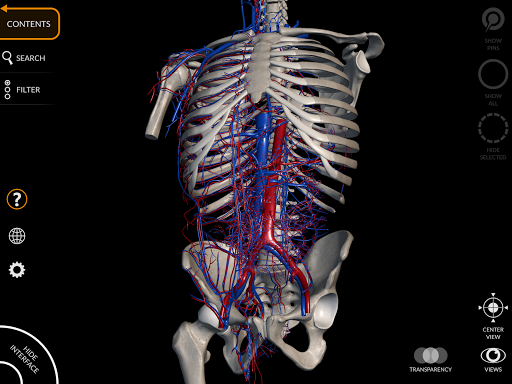

"Anatomía - Atlas 3D" permite estudiar la anatomía humana de forma fácil e interactiva.

A través de una interfaz sencilla e intuitiva es posible observar cada estructura anatómica desde cualquier ángulo.

Los modelos anatómicos 3D son especialmente detallados y con texturas de hasta una resolución de 4k.

La subdivisión por regiones y las vistas predefinidas facilitan la observación y el estudio de partes individuales o grupos de sistemas y las relaciones entre los diferentes órganos.

• Sistema cardiovascular • Sistema

nervioso • Sistema respiratorio • Sistema digestivo • Sistema urogenital (masculino y femenino) • Sistema endocrino • Sistema linfático • Sistema ocular y auditivo CARACTERÍSTICAS • Interfaz sencilla e intuitiva • Rotar y hacer zoom en cada modelo en el espacio 3D • Opción para ocultar o aislar uno o varios modelos seleccionados • Filtro para ocultar o mostrar cada sistema • Función de búsqueda para encontrar fácilmente cada parte anatómica • Función de marcador para guardar vistas personalizadas • Rotación inteligente que mueve el centro de rotación automáticamente • Función de transparencia • Visualización de músculos a través de niveles de capas desde las superficiales hasta las más profundas • Al seleccionar un modelo o un pin, aparece el término anatómico relacionado • Descripción de los músculos: origen, inserción, inervación y acción • Mostrar/ocultar interfaz de usuario (muy útil con pantallas pequeñas) MULTILINGÜE • Los términos anatómicos y la interfaz de usuario están disponibles en 11 idiomas: latín, inglés, francés, alemán, italiano, portugués, turco, ruso, español, Chino, japonés y coreano • Los términos anatómicos se pueden mostrar en dos idiomas simultáneamente REQUISITOS DEL SISTEMA • Android 8.0 o posterior, dispositivos con al menos 3 GB de RAM Reversi